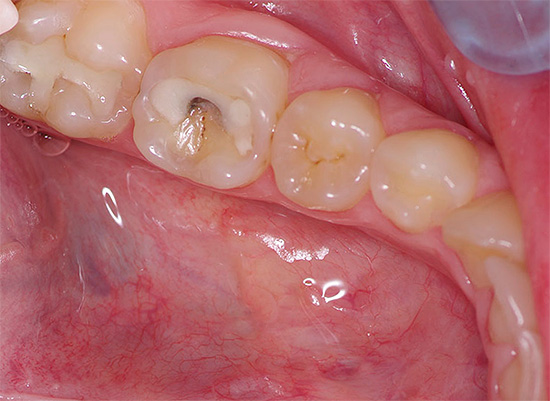

Mas na maioria das vezes os dentes doem devido a várias patologias: devido a cárie profunda, pulpite ou periodontite, e nesses casos a dor pode variar de leve e rápida a muito aguda e constante. Além disso, também pode ser observado inchaço das gengivas e bochechas (edema), febre, dor de cabeça e outros sintomas desagradáveis.

- Cárie, que em diferentes estágios pode se manifestar como dor fraca e que passa rapidamente, e dor bastante forte. Se você suprimir essa dor de dente em casa com pílulas, o processo de cárie inevitavelmente chegará à polpa, resultando em pulpite - e essa é uma dor muito mais intensa, e o tratamento desse dente estará associado à necessidade de remover o "nervo" dele. Geralmente, esse é um procedimento longo e caro, especialmente no caso de dentes multicanais.

- A pulpite, que se manifesta com dor de dente grave, geralmente piora à noite. Se, neste caso, você tentar ser tratado em casa, apenas aliviando a dor com a ajuda de comprimidos, poderá praticar periodontite, fluxo e fístulas purulentas nas gengivas. Além disso, em alguns casos, a extração dentária está longe de ser a conseqüência mais triste.